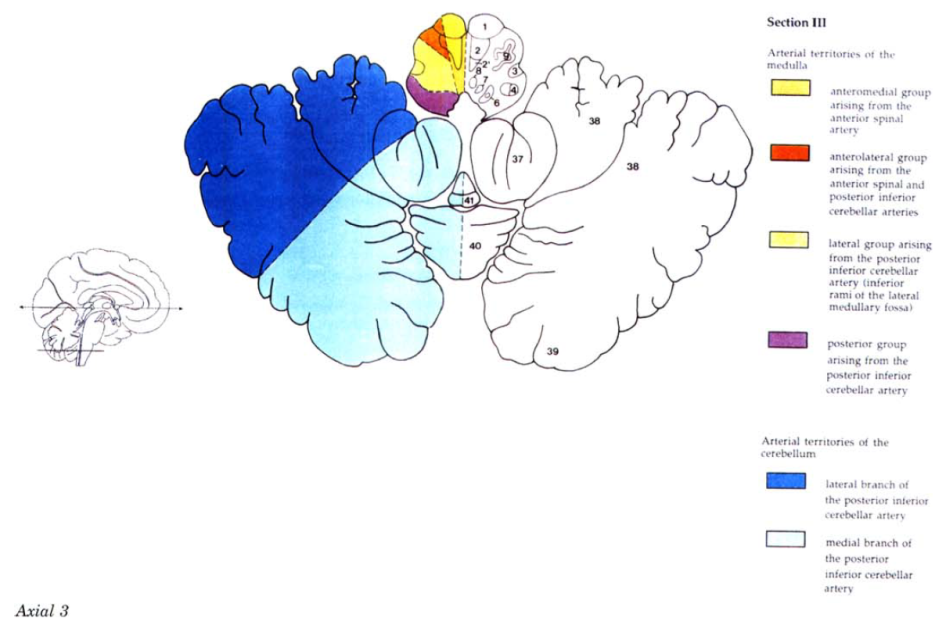

Cerebral vascular territories

Brainstem